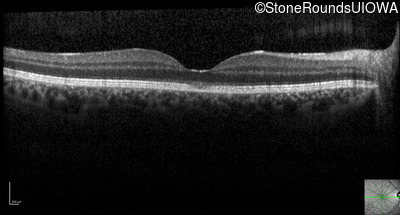

Optical Coherence Tomography - Left - 20/50 sc

Exemplar / OCT Stack

OCT Stack